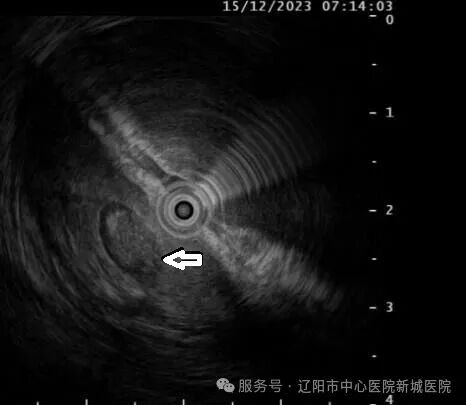

超声内镜:胃壁第2、3层内见一椭圆形混合回声

5天前,王女士误服枣核,之后出现上腹部隐痛,进行性加重,并伴有发热、恶心等症状,自服多种胃药治疗,症状未改善。来院就诊行胃镜检查提示:胃窦大弯侧见一约1.5cmX1.0cm的广基隆起,表面粘膜光滑。进一步行超声内镜扫查显示:胃壁第2、3层内见一椭圆形混合回声区域,边界清晰,切面大小约1.0cmX0.5cm,结合病史,确诊为胃脓肿。